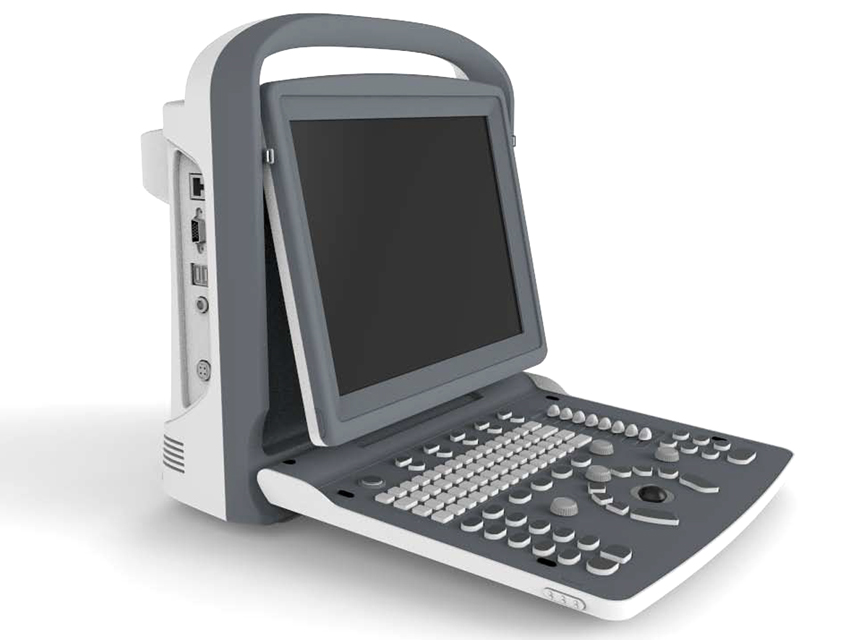

ECO2 Powerful, affordable black-and-white ultrasound scanner

- compact and lightweight, easy to carry

- screen with new generation LED technology; ultra-bright images allow optimal viewing even outdoors

- ergonomic monitor design, 30 degree rotation, adjustable

- long battery life of up to 2.5 hours, for outdoor use

- full screen image magnification, for better viewing at a distance

- straightforward, user-friendly workflow, 6 quick keys to finalise the diagnosis cycle

User interface

- foldable control panel and alphanumeric keyboard

- backlit keypad for optimal visibility in the dark

- illuminated indicators identify activated keys

- 8 TGCs for easy adjustment

- user-defined hotkey for quick adjustment

- clear and intuitive keyboard layout, quick to memorise

- interactive backlighting - user-defined settings

Screen: 12" LED, high resolution 1024x768

3 USB ports, 1 Ethernet port

1 video port, 1 VGA port, 1 footswitch port